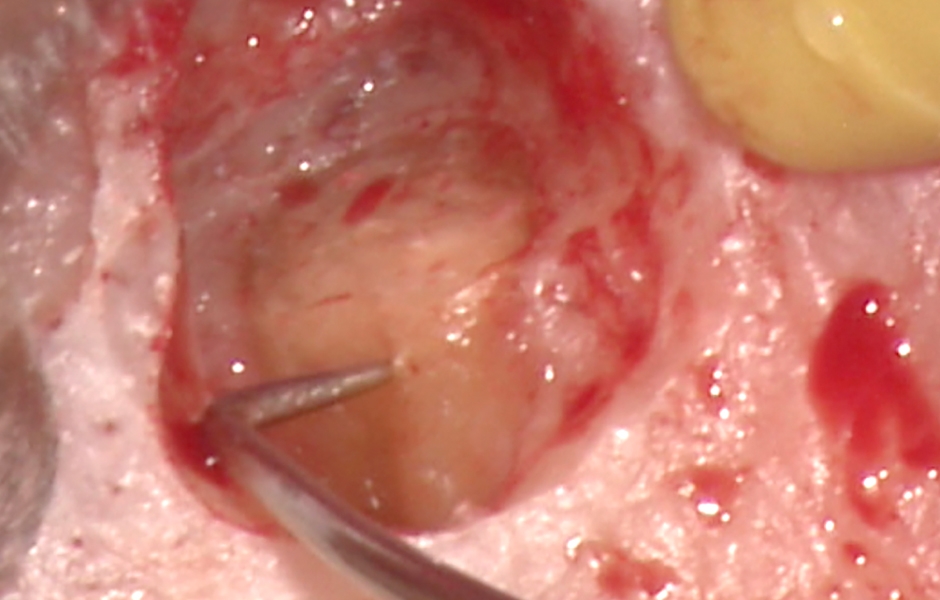

Obr. 1.2: Submarginální incize.

Obr. 4.2: Submarginální lalok.